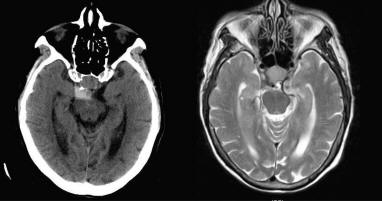

With bleed into pituitary tumor with sudden visual disturbance. Requires emergency surgery. Macroadenoma Large tumor, usually non- secreting (hormone levels are normal), cause headache or visual disturbance Microadenoma Small tumor, usually secretes ... Read Content

Pituitary Apoplexy! Bleeding into the pituitary gland! Usually involves bleeding into an adenoma! Typical presentation (mild symptoms to . sudden death) ... Retrieve Content

Midbrain hemorrhage mimicking pituitary apoplexy in patient using anticoagulation therapy Leonardo M. Batista1, Daniel M. Prevedello2, Contrast CT-scan. Pituitary adenoma [A] is visualized (white arrow). There is evidence of a previous transsphenoidal resection. Axi- ... Retrieve Document

Pituitary Apoplexy With Intraventricular Hemorrhage: Clinical ...

518 Adriana Dediu et al Pituitary apoplexy with intraventricular hemorrhage heterogeneous intensity of hemorrhage, edematous pituitary gland, and necrotic ... Retrieve Document

Optic Tract Hemorrhage After Pituitary Apoplexy

CASE REPORT Optic Tract Hemorrhage after Pituitary Apoplexy H.J. Kim W.H. Cho SUMMARY: Subarachnoid hemorrhage following pituitary apoplexy is suggestive of a subacute bleed. Note that neither the optic chiasm nor the optic tracts reveal evidence of hemorrhage on T1-weighted (A, B) or T2 ... Access This Document